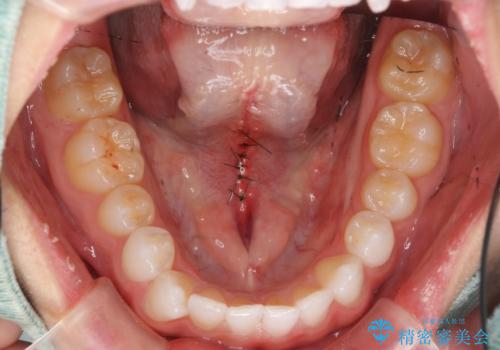

- 舌小帯の切除を希望して来院。

口を大きく開けた時に、上顎に舌がつかない状態でした。